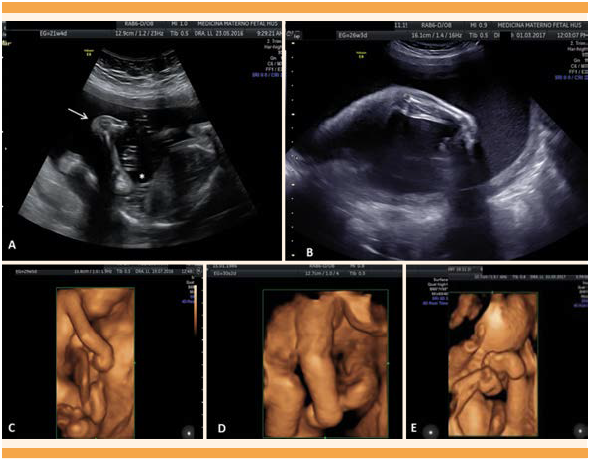

Las imágenes muestran los hallazgos ultrasonográficos en 2D observándose en la letra A. Posición anómala de la rodilla (*) y pie equino varo (flecha), caso 1. La letra B muestra contractura en la flexión de la muñeca y de los dedos de la mano del caso 8. Las imágenes restantes corresponden a ecografías en 3D, letra C (caso 1), letra D (caso 5), letra E (caso 8), observándose malposición articular en los miembros superiores (codos, muñecas y dedos), caderas y miembros inferiores con contracturas evidentes a nivel en las rodillas y tobillos, con deformidades en los pies.

Figura 2 Hallazgos ultrasonográficos en 2D-3D de los casos evaluados.